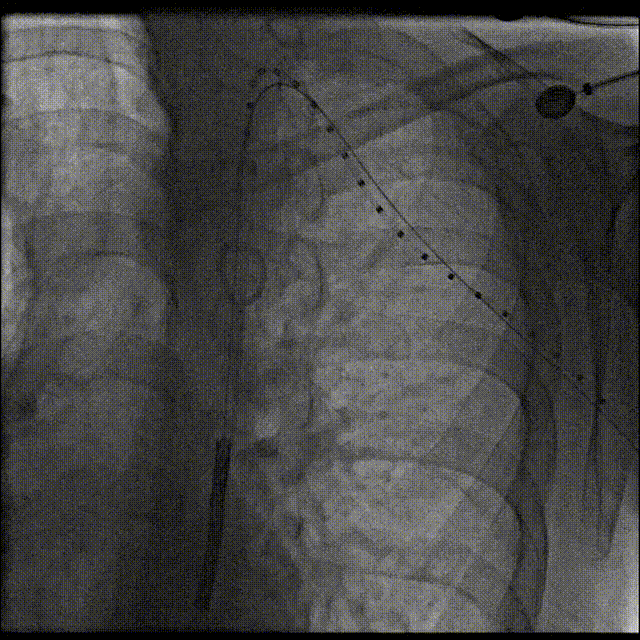

关键步骤:穿通闭塞离断部位。股动脉逆行途径将6F长鞘头端送至降主动脉离断起始部,5F MPA导管及泥鳅导丝经长鞘至离断端,长鞘支撑下,泥鳅导丝配合MPA导管轻柔操作,反复尝试,将260cm0.032‘Terumo软泥鳅导丝和5FrMPA导管逆行穿通闭塞离断部位至左锁骨下动脉。

导丝逆行通过弓离断处